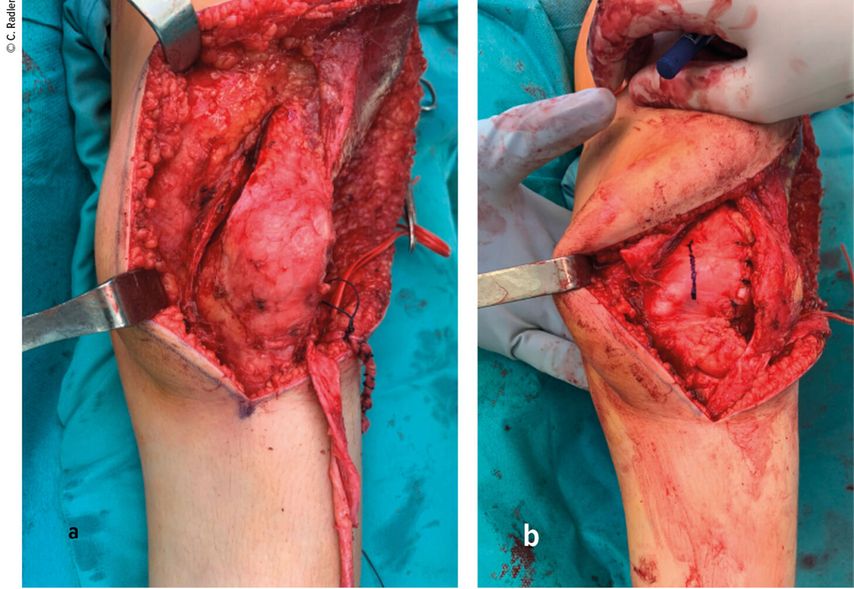

Modifizierte Operation nach Langenskiöld

Bei der modifizierten Operation nach Langenskiöld wird die Gelenkkapsel medial und lateral der Patella inzidiert und der Vastus-medialis-Ansatz von der Patella gelöst. Die Synovia muss dabei intakt gelassen werden. Die Kapsel wird medial auf Höhe des Gelenkspaltes transversal eingeschnitten (Abb. 5a). Die gesamte Synovia wird sorgfältig von der Kapsel getrennt. Zur Korrektur der Lateralisation des Ansatzes wird die Patellasehne am Tuberculum im Sinne einer Korrektur nach Grammont scharf abgelöst und nach medial verschoben. Dabei darf weder nach zu distal geschnitten werden, um die Sehne nicht gänzlich abzulösen, noch zu tief, da dies die Apophyse verletzen könnte. Schließlich wird die Synovia um die Patella herum inzidiert und von der Synovia gelöst. Die zurückbleibende Öffnung wird dicht vernäht und sodann wird im Bereich der Notch eine neue und physiologische Position für die Patella gefunden (Abb.5b). Hier wird nun die Patella über die Synovia eingenäht. Allein dieser Schritt führt zu einer beeindruckenden Primärstabilität. Im letzten Schritt wird die mediale Kapsel mit dem Vastus medialis an beziehungsweise auf der Patella fixiert und der mediale Teil der Patellasehne an die Tuberositas tibiae medialisiert vernäht. Diese extrem effektive OP-Technik kann auch bei anderen habituellen Patellaluxationen, auch bei Vorliegen einer dysplastischen Notch, durchgeführt werden.7